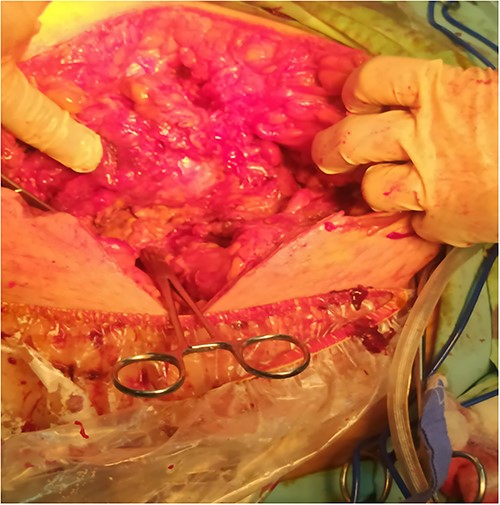

A 53-y-old morbidly obese female patient (BMI = 50) was diagnosed with colicky abdominal pain that progressively worsened over 1 week and became constant, without clear exacerbating or relieving factors. She also complained of fever, constipation, nausea, vomiting and anorexia. Past surgical history was significant for a surgically repaired umbilical hernia 10 y ago. The pain gradually became continuous and more severe, warranting hospital admission for further evaluation. On physical examination, the patient appeared unwell, dehydrated, and severely distressed. Vital signs showed a blood pressure of 100/60 mm Hg, pulse of 90 bpm and a temperature of 38 °C. Oxygen saturation was 95% on ambient air. Abdominal examination revealed midabdominal tenderness with mild abdominal distension, as well as high-pitched bowel sounds. Notably, there was an infected wound measuring 20 cm × 13 cm on the midline of the abdomen with signs of poor healing, tissue necrosis, and foul-smelling discharge (Fig. 1). Rectal examination was inconclusive. Laboratory tests indicated elevated levels of inflammatory markers, including a C-reactive protein (CRP) level of 445 mg/L and a white blood cell count of 30 000/ml. Hemoglobin level was 7.8 g/dl with a mean corpuscular volume (MCV) of 65. Additional abnormal results included a creatinine level of 1.8 mg/dl and a random blood sugar level of 310 mg/dL. Electrolyte levels were normal. Based on the laboratory findings, the LRINEC score was calculated to be 11, suggesting a high risk of NF. A plain abdominal X-ray showed fluid levels in the small intestine but no signs of pneumoperitoneum (Fig. 2). Abdominal ultrasound revealed localised swelling and fluid accumulation in the anterior abdominal wall, with dilated and edematous small intestine loops trapped within. The patient was ultimately diagnosed with strangulated incisional hernia complicated by NF of the abdomen. Management included nasogastric decompression, intravenous fluids and broad-spectrum antibiotics. Subsequently, the patient underwent emergency wound debridement under general anesthesia using a left paramedian laparotomy incision (Fig. 3). During the procedure, necrotic and dark skin, as well as friable subcutaneous tissue, were observed and resected (Figs 4 and 5). Approximately 500 ml of pus and digested food particles were drained from the abdominal wall. Controlled irrigation of the wound with saline was performed, and the strangulated bowel was identified, resected, and a loop ileostomy was created. There was no contamination of the peritoneal cavity. Two surgical drains were inserted, one in the abdominal wall and one in the peritoneal cavity. As the wound was considered contaminated, the fascia was sutured, but the skin edges were approximated and left open for secondary healing (Fig. 6). A temporary cover was applied using a plastic sheath (Fig. 7). The patient was then transferred to the intensive care unit (ICU) for continued postoperative wound care and debridement. On the 7th day, the patient was started on a soft diet and referred to the plastic surgery unit for ongoing wound treatment.

Suture approximation technique was done. At the site of maximum skin necrosis, the wound is left open for secondary healing, with a drain inserted in the abdominal wall.